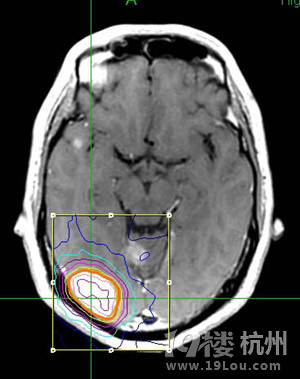

颅内多发转移瘤射波刀怎么治-网上问医-杭州1

300x379 - 32KB - JPEG

300x370 - 31KB - JPEG

300x226 - 36KB - JPEG

300x204 - 28KB - JPEG